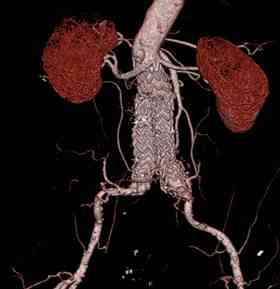

Figura 3. Angio-TC de control: Corte axial en lado izquierdo y su reconstrucción en 3D en lado derecho donde se demuestra exclusión del aneurisma con permeabilidad tanto de las chimeneas renales como del resto de arteriales viscerales, sin endofugas ni desplazamientos de la prótesis.